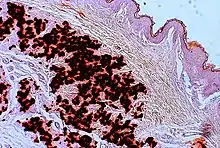

The diagnostic criteria for PXE are the typical skin biopsy appearance and the presence of angioid streaks in the retina. Criteria were established by consensus of clinicians and researchers at the 2010 biennial research meeting of the PXE Research Consortium.[29] and confirmed at the 2014 meeting[30] These consensus criteria state that definitive PXE is characterized by two pathogenic mutations in the ABCC6 or ocular findings – angioid streaks > 1 DD or peau d’orange in an individual <20 years of age together with skin findings:

- Diagnostic histopathological changes in lesional skin: Calcified elastic fibers in the mid and lower dermis, confirmed by positive calcium stain

| Pseudoxanthoma elasticum | LM: Mid-dermal calcification and fragmentation of elastic fibers EM: Mineralization in elastic fiber core |

| PXE-like papillary dermal elastolysis | LM: Selective elastic tissue elimination in the papillary dermis and presence of melanophages |

| Perforating calcific elastosis | LM: Middermal calcification and degeneration of elastic fibers with transepidermal elimination |